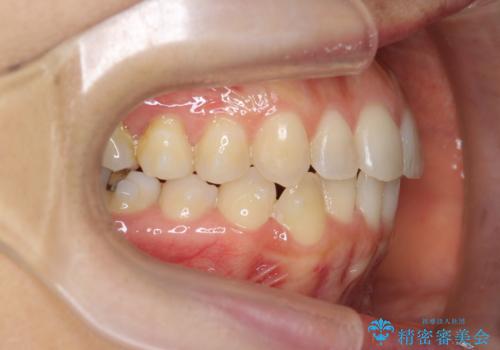

前歯のがたつきをしっかり治すマウスピース矯正

- 前歯のガタガタをきれいに並べたい、と希望され来院されました。

マウスピース矯正インビザラインのクリンチェックを用いて治療前にしっかりと歯並びのゴールのシミュレーションを行い、治療を開始します。

がたつきのないきれいな歯並びに仕上げることができ、満足いただくことができました。